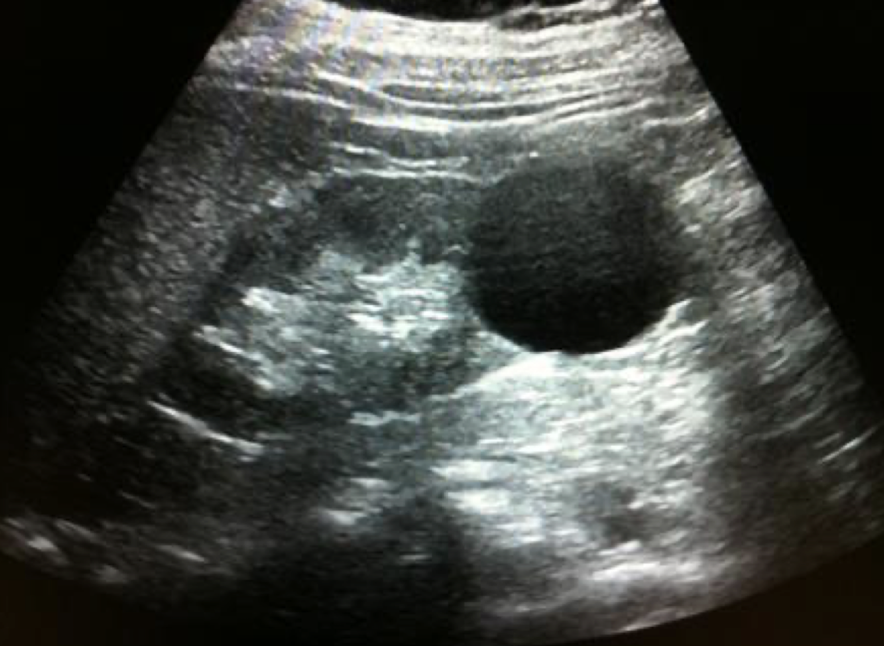

cystic mass

anechoic

smooth, thin, well-defined

round or oval shape

sharpe interference between cyst and renal parenchyma

increased posterior acoustic enhancement

describe

“cystic structure with posterior enhancement measuring 3 cm x 3 cm x 3 cm noted in LP or RK”

simple renal cyst

MC renal mass lesion

occur in 50% of population

solitary or multiple

s/s: asymptomatic—often incidental finding